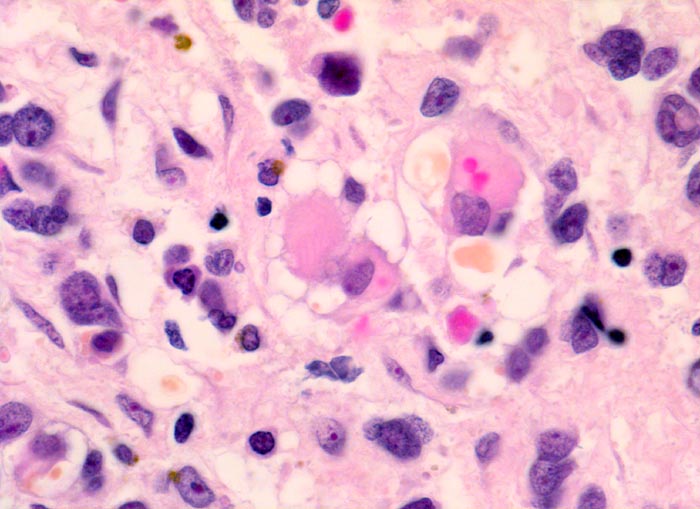

Das makroskopische Bild ist uncharakteristisch und variiert in Abhängigkeit von der Lokalisation. Fokale Nekrosen und zystische Degeneration sind häufig. Es werden verschiedene histologische Subtypen unterschieden, welche charakteristische molekulargenetische Aberrationen aufweisen und mit unterschiedlichen Prognosen assoziiert sind. Die beste Prognose haben botryoide und spindelzellige Rhabdomyosarkome gefolgt von embryonalen Rhabdomyosarkomen (intermediäre Prognose) und alveolären bzw. pleomorphen Rhabdomyosarkomen (schlechteste Prognose). Therapieantwort und Prognose hängen neben der Histologie auch von der Lokalisation ab. Embryonale Rhabdomyosarkome zeigen ein breites morphologisches Spektrum. Dieses reicht von wenig differenzierten Tumoren, die nur mittels Immunhistochemie und Elektronenmikroskopie diagnostizierbar sind zu gut differenzierten Tumoren, die fetaler Muskulatur ähneln. Oft findet sich eine Mischung von wenig differenzierten kleinen, runden und/oder spindeligen Zellen und eine variable Anzahl differenzierter Rhabdomyoblasten mit reichlich eosinophilem Zytoplasma. Die Rhabdomyoblasten können rund, spindelig, kaulquappenförmig oder spinnwebenförmig sein. Besser differenzierte Zellen enthalten reichlich Zytoplasma mit Querstreifung, welche allerdings teilweise nur elektronenmikroskopisch nachweisbar ist.

• Konjunktivalschleimhautfragment. Fibrinauflagerungen anstelle der langstreckig abgeschilferten konjunktivalen Zylinderepithelbedeckung (unten).

• Chronisches lymphoplasmazelluläres Entzündungsinfiltrat im subepithelialen Stroma mit unscharfer Begrenzung zu einem zellreichen soliden Tumor.

• Dieser besteht aus mesenchymalen Zellen mit unterschiedlicher Ausdifferenzierung.

• Die am wenigsten ausdifferenzierten Zellen zeigen wenig amphophiles Zytoplasma und ovale Kerne.

• Dominierend sind in diesem Tumor teils mehrkernige Rhabdomyoblasten mit reichlich eosinophilem Zytoplasma und exzentrischem Zellkern. Die Querstreifung des Zytoplasmas ist in der HE Färbung nur andeutungsweise erkennbar.

• "Spinnwebenzellen" mit peripheren Zytoplasmavakuolen.